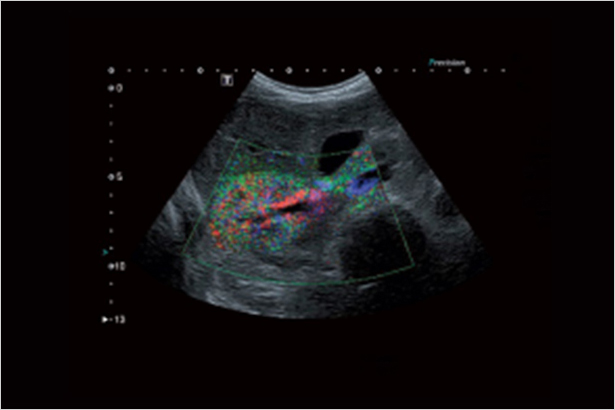

FLEX-M組件通過對視野內彩色像素數量的計算,定量評估血流豐富程度

ADF運用寬頻帶窄脈沖技術讓多普勒成像模式具有敏感度和空間分辨率